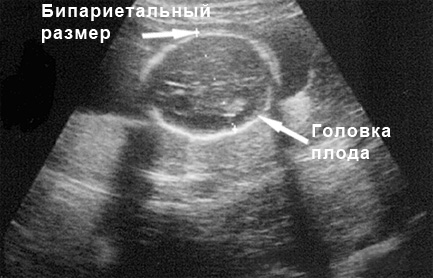

УЗИ на 18 неделе беременности

Плановое ультразвуковое исследование на 18-й неделе беременности не проводится – обычно оно назначается на 20-22 неделях. На этом этапе УЗИ выполняется по медицинским показаниям, если есть подозрения на возможные аномалии развития плода. На 18-й неделе с помощью ультразвука можно обнаружить характерные признаки различных пороков, включая синдром Дауна. Кроме того, измерения размеров плода на этом сроке помогают установить точные даты беременности.

Ожидаемые результаты УЗИ на данном этапе должны быть примерно следующими:

БПР (бипариетальный размер головы – расстояние между теменными буграми) – 39 мм;

ОЖ (окружность живота) – 108 мм;

ДБ (длина бедра) – 27 мм.

На 18-й неделе также есть возможность с большей вероятностью определить пол вашего будущего ребенка, однако с полной уверенностью говорить о половой принадлежности пока нельзя – это зависит от того, насколько хорошо врач сможет увидеть половые органы малыша. Сделать это бывает непросто, так как дети на этом сроке очень активны.

Помимо оценки развития плода, ультразвук позволяет оценить состояние шейки матки и положение плаценты, которая в норме должна находиться у дна матки, прикрепляясь к передней или задней стенке. Если плацента расположена на боковой стенке матки, существует вероятность, что по мере роста беременности она может подняться выше из-за растяжения стенок матки. При аномальном прикреплении плаценты, особенно при полном предлежании, беременной женщине может потребоваться изменить образ жизни, ограничив физические нагрузки и сексуальные контакты. Роды при полном предлежании плаценты осуществляются исключительно с помощью кесарева сечения.